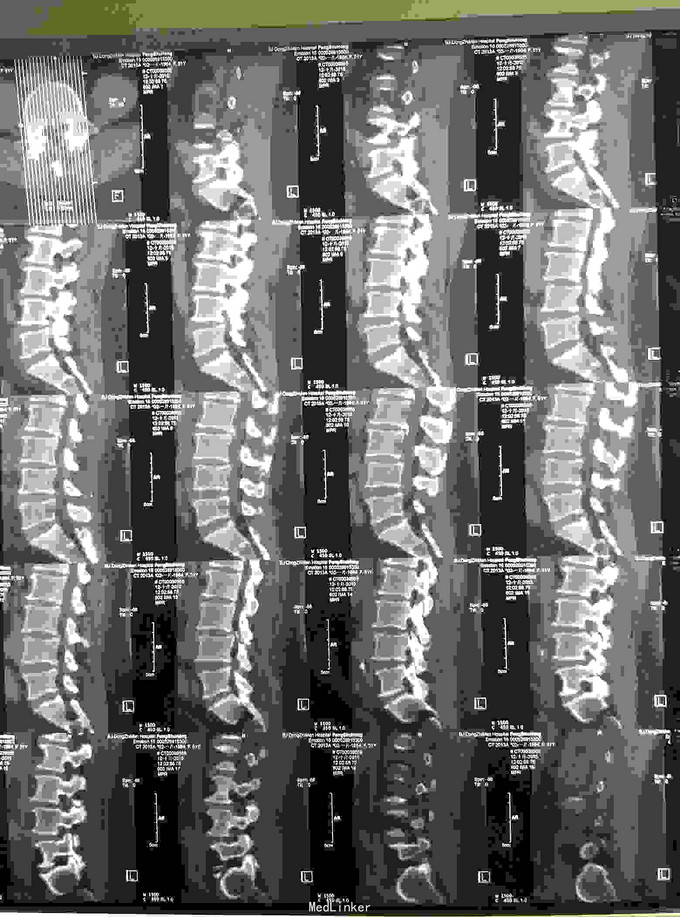

腰椎生理曲度变直,腰骶部压痛明显,叩痛明显,双下肢直腿抬高试验左60度,右80度,股神经牵拉试验阴性,双下肢膝腱反射,跟腱反射正常,会阴区感觉正常,肛门反射正常,双下肢血运感觉对称无异常。腰椎ct及MRI示:腰34、45,51间盘突出,椎管狭窄,相应硬膜囊及神经根受压。

腰椎间盘突出,腰椎管狭窄,完善检查,于手术室全麻下行腰椎后路腰4-5,腰5-骶1椎板部分切除,髓核摘除,椎管减压,椎弓根内固定术,术后给予抗炎,消肿,止痛,抗感染对症治疗